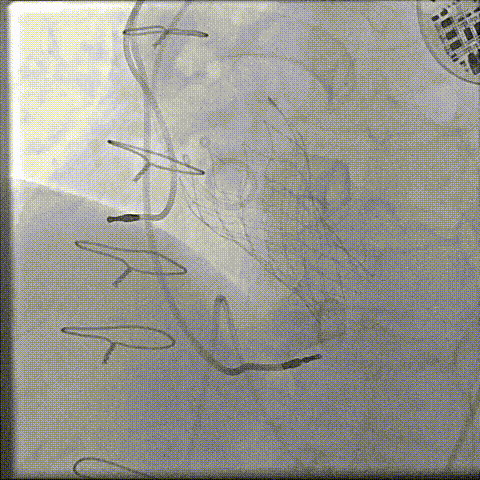

22mm球囊后扩(1.0倍速播放)